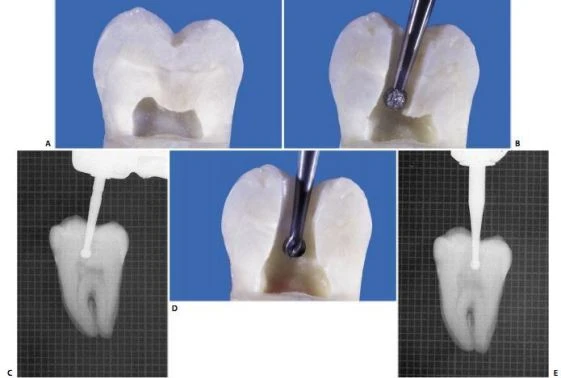

Cần lưu ý rằng khi tạo xoang tủy thì không nên tạo hình tam giác (theo một số tác giả có mô tả) mà nên tạo hình tứ giác hoặc hình như hình ¼ vòng tròn với các góc được làm tròn. Hình dạng tam giác cổ điển có thể cản trở việc nhận biết sự hiện diện của ống tủy thứ 2 ở chân xa (Ví dụ ống tủy xa trong) và cũng cản trở việc làm sạch và tạo hình  những ống tủy đã được bộc lộ (hình 11.114).

Hình 11.114. A. Lối vào tủy hình tam giác. B. Mặc dù độ hẹp của  nó, dụng cụ cũng có thể vào ống tủy; tuy nhiên hoạt động của dụng cụ bị cản trở ở phần gần miệng vào lỗ ống tủy. C. Xoang tủy được mở rộng, loại bỏ hoàn toàn trần buồng tủy. D. Dụng cụ đi thẳng đến 1/3 chóp mà không gặp phải trở ngại ở phần miệng ống tủy. Chú ý rằng không liên quan đến đỉnh múi.

Chỉ khi chỉ có một ống xa khá tròn thì mới nên tạo xoang tủy có hình tam giác (hình 11.114 C). Trong tất cả những trường hợp khác, hình dạng xoang tủy nên là hình tứ giác với cạnh nhỏ hơn tương ứng thành xa.